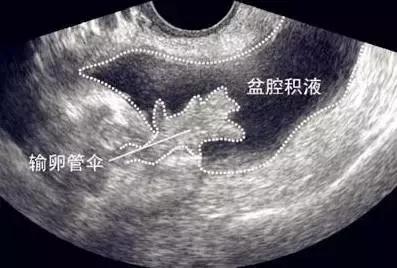

女性如果出现小腹下坠感,下腹、腰骶部疼痛,抵抗力下降,月经紊乱,不孕,这时候不可排除盆腔积液的可能,就诊时妇科常用的有效检查手段是B超,可以较准确的判断积液的量。